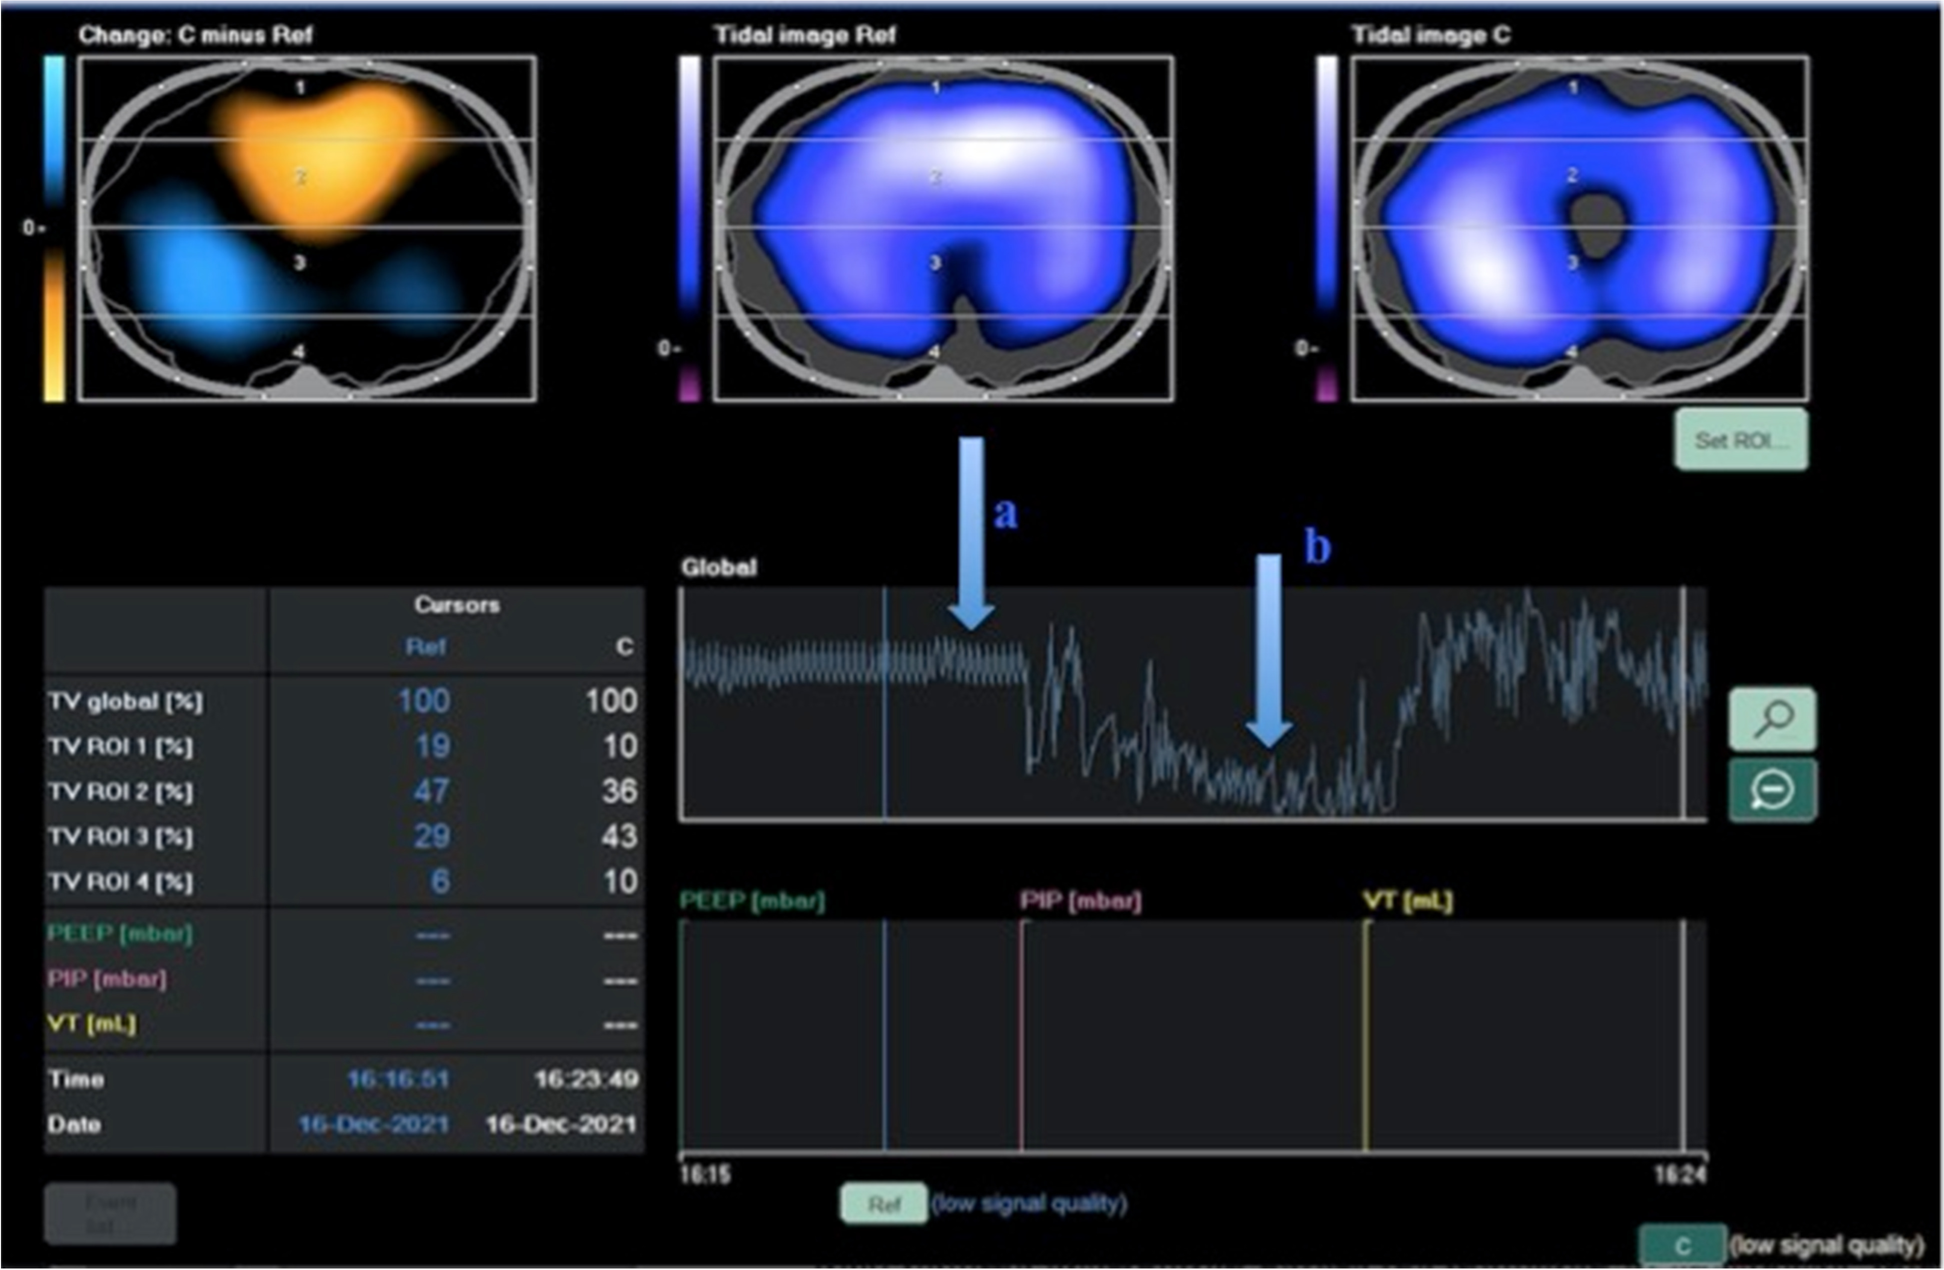

Fig. 2

From spontaneous breathing (a) to induction of anesthesia and ventilation in bag mask (b) and controlled mechanical ventilation, followed by the application of an external PEEP (c)

Post-extubation period

EIT also allows for the continuous monitoring of patients in the postoperative period (Fig. 3). The end of surgery and subsequent post-extubation phase are times that require close monitoring due to the abrupt discontinuation of mechanical ventilation and loss of respiratory monitoring that was provided by the ventilator. In addition, these changes coincide with the persisting consequences of sedation, including muscle weakness, reduced inspiratory effort and transpulmonary pressure, an impaired cough reflex and ability to clear secretions due to residual paralysis, and/or poor pain control. Altogether, these factors contribute to an increased risk of postoperative pulmonary complications, which might easily be identified by monitoring changes in ventilation distribution and EELI measured by EIT, especially at the end of the surgical procedure. Schaefer et al. [69] described the feasibility of using EIT to monitor regional tidal volume distribution before the induction of anesthesia, intra-operatively, after extubation, and in the post-operative period. The authors showed that during general anesthesia, tidal ventilation is distributed to the ventral part of the lungs due to muscle paralysis. When spontaneous breathing is restored and following extubation, ventilation, and re-aeration of the dorsal part of the lungs take place, increasing the homogeneity of ventilation, decreasing the tendency for atelectasis. Interestingly, despite using a personalized intra-operative PEEP setting and a recruitment maneuver before extubation, early post-operative EELV is lower compared to baseline before induction of anesthesia [66]. A decrease in EELV at the end of surgery might represent an “alarm bell” that suggests an increased risk of developing postoperative atelectasis and extubation failure. For this reason, EIT monitoring can help to identify patients with a reduced post-operative EELV who might benefit from post-extubation non-invasive ventilation and early mobilization (i.e., obese patients) [76]. Karsten et al. used EIT to evaluate the impact of low versus high PEEP during laparoscopic surgery on post-operative ventilation distribution and showed that a higher intra-operative PEEP resulted in a more homogeneous distribution of ventilation in the early post-operative period [77].

Fig. 3

In the first part of the recording, the patient was still intubated and under controlled mechanical ventilation (a). After the weaning process, it is possible to follow the extubation period and the patient breathing spontaneneusly (b), followed by the application of a postoperative CPAPs